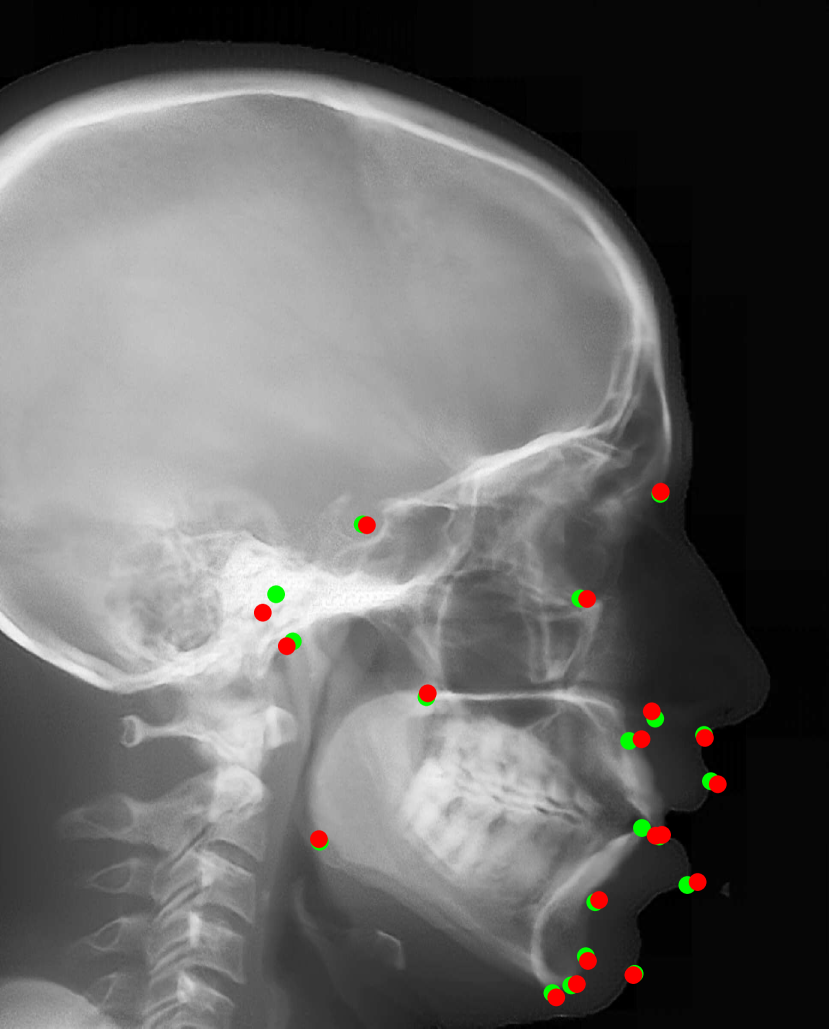

Refer to caption

Fig. 15: Accuracy comparison of different cephalometric landmark detection algorithms [16, 27, 1, 40, 7, 46] on ISBI Testset1 and Testset2.

To validate the efficacy of our proposed automatic landmark detection algorithm, it is compared with other state-of-the-art algorithms on the benchmark ISBI data (Testset1 and Testset2). The SDRs of different algorithms [16, 27, 1, 40, 7, 46] in different precision ranges for Testset1 and Testset2 are displayed in Fig. 15(a) and (b), respectively. Our proposed method achieves the 2 mm-SDRs of 86.7% and 73.7% on the ISBI Testset1 and Testset2, respectively, which is comparable to the best accuracy methods [7, 46]. However, our method is more efficient than [7] and has a simpler architecture than [46].

Fig. 16: Landmark detection on synthetic cephalograms. Cephalograms in the top row are obtained by different synthesis methods from 3D volumes for the first patient with pix2pixGAN for SR. The second row shows Type I synthetic cephalograms with different SR methods. The 3rd and bottom rows are Type I and Type II synthetic cephalograms respectively from three example patients with pix2pixGAN for SR. The green (reference) and blue labels are manual detection landmark positions in Type I and Type II synthetic cephalograms respectively, while the red labels are automated detection landmark positions in each cephalogram.

Our proposed landmark detection method is applied to detect landmarks in synthetic cephalograms. The results of three example patients are displayed in Fig. 16. Cephalograms in the top row are obtained by different synthesis methods from 3D volumes for the first patient with pix2pixGAN for SR. The second row shows Type I synthetic cephalograms with different SR methods. The 3rd and bottom rows are Type I and Type II synthetic cephalograms respectively from three example patients with pix2pixGAN for SR. The green and blue labels are manual detection landmark positions in Type I and Type II synthetic cephalograms respectively, while the red labels are automated detection landmark positions in each cephalogram. The green labels are used as the reference. The overall SDRs of the landmarks in different types of synthetic cephalograms on the test patients are displayed in Tab. 4. The last row SDRs are calculated from manual detection (blue) landmarks in Type II synthetic cephalograms w. r. t. reference landmarks, while others are from automatic detection (red) landmarks w. r. t. reference landmarks.

For RayCast in Fig. 16(a), many automatic detection landmarks exceed the 4 mm precision range such as the landmarks of anterior nasal spine, gonion, porion and articulare. According to Tab. 4, overall only 45.6% landmarks are detected within the 4 mm precision range by the automatic landmark detection algorithm. For MIP100 in Fig. 16(b), the landmarks of sella, porion, articulare have very large deviations from the reference landmarks. Overall, it achieves 47.4% 2 mm-SDR and 81.5% 4 mm-SDR. Figs. 16(c) and (g) are the cephalograms synthesized by our Type I synthesis with the original sigmoid transform and the modified sigmoid transform, respectively. These two synthetic cephalograms have subtle difference in the soft-tissue areas. As a result, the detected incision superius and lower lip positions exceed the 4 mm range in Fig. 16(c) while they are well detected within the 2 mm precision range in Fig. 16(g). This demonstrates the benefit of the modified sigmoid transform.

In Figs. 16(d)-(f), the landmark detection accuracies are very close to each other for the other 18 landmarks except for the sella landmark. The point-to-point errors are 9.77 mm, 4.57 mm, and 1.65 mm respectively in Figs. 16(d)-(f) for the sella. Tab. 4 indicates that overall 66.7% landmarks are detected within the 2 mm precision range for bicubic interpolation. For ESRGANRDB and ESRGANRRDB using ILR patches, the 2 mm-SDR rises to 70.2% and 71.9%, respectively. Nevertheless, pix2pixGAN achieves the best 2 mm-SDR 75.4% among different SR methods for Type I synthesis. Therefore, different SR methods have an influence on the landmark detection.

For Type I synthesis, two more cephalograms are displayed in Figs. 16(h) and (i). Overall, 93.0% automatic detection landmarks are overlapped with the reference landmarks within the precision range of 4 mm, with a few exceptions such as the sella landmark in (g), the porion in (h), and the incision inferius and subnasale landmarks in (i) beyond 4 mm. Particularly, 75.4% automatic detection landmarks are within the 2 mm clinical acceptable precision range. This indicates that the automatic landmark detection algorithms learned from real conventional cephalograms can be applied to our Type I synthetic cephalograms.

For Type II synthetic cephalograms in Figs. 16(j)-(l), all the manual detection (blue) landmarks are overlapped with the reference landmarks within the distance range of 4 mm, indicating that the landmark positions in the Type II synthetic cephalograms have no impactful position shift from those in Type I synthetic cephalograms. The majority (80.7%) of the automatic detection (red) landmarks are also overlapped with the reference landmarks within the 4 mm precision range. However, more automatic detection landmarks in Type II synthetic cephalograms are outside the 4 mm range than those in Type I synthetic cephalograms, for example, the anterior nasal spine landmark in (j), the orbitale landmark in (k), the incision inferius landmark in (l), the nasion landmarks in (k) and (l), and the gonion landmarks in (j)-(l). The 2 mm-SDR also decreases from 75.4% to 50.9%.